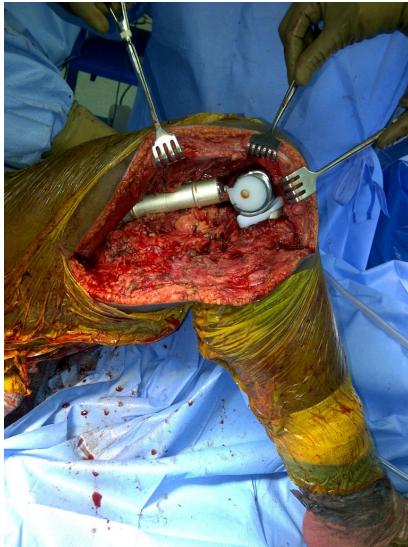

Resection & Reconstruction